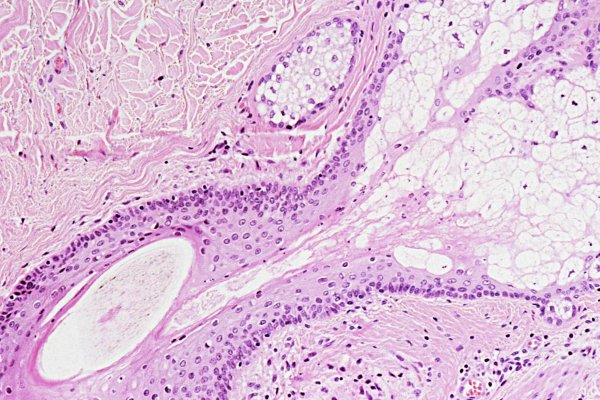

2020年9月份,生物学家在研究癌细胞的过程中,意外发现人体存在未知新器官,而这个新器官位于鼻子到咽喉这里面,只有3.9公分大小。划重点是新器官属于唾液腺中一种,名字叫着管状腺 。随后生物学家把这一发现整理成论文,并且发布在《放射性治疗与肿瘤学》杂志上面。

除此之外,生物学家还进行大量的实验证明,这个新器官是真的存在,而不是个别人才拥有的。生物学家成立一个研究小组,召集了100名实验者,对他们进行研究测试,都做了PSMA PET-CT,最后结果显示新器官都存在,是人体的一部分,谁都拥有这个器官。